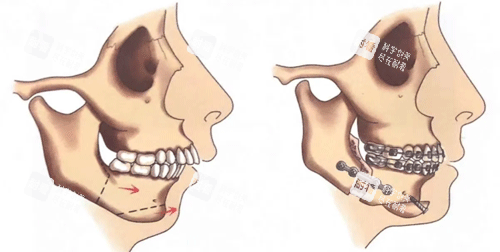

正畸正颌联合治疗是一种将正畸治疗和正颌手术相结合的治疗方法,它充分发挥了正畸和正颌手术各自的优势,能够更有效地矫正骨性嘴凸。

在正畸正颌联合治疗中,正畸治疗通常是治疗的头一步。正畸医生会根据患者的具体情况,为患者佩戴合适的牙套,通过施加一定的力量来调整牙齿的位置和排列。这一步的目的主要有两个,一是为正颌手术创造有利的条件,比如将牙齿排齐、调整咬合关系等,使手术能够更加顺利地进行;二是在一定程度上改善牙齿的外观,为后续的正颌手术打下基础。

正颌手术则是在正畸治疗进行到一定阶段后进行。外科医生会根据正畸医生提供的牙齿和颌骨的模型、影像学资料等,制定详细的手术方案。手术中,医生会通过正确的操作将颌骨移动到合适的位置,并进行固定。正颌手术能够从根本上解决颌骨发育异常的问题,从而显著改善嘴凸的情况。

正畸正颌联合治疗能够显著改善面部轮廓。通过调整颌骨的位置,嘴巴向前突出的情况得到明显改善,嘴唇能够自然闭合,侧面看起来更加协调。原本不流畅的面部线条变得更加柔和、美观,面部的立体感也会增强。比如,一些患者在治疗前侧面看起来下巴后缩,经过正畸正颌联合治疗后,颌骨位置得到调整,下巴的形态也会更加自然,整个面部的比例更加协调。